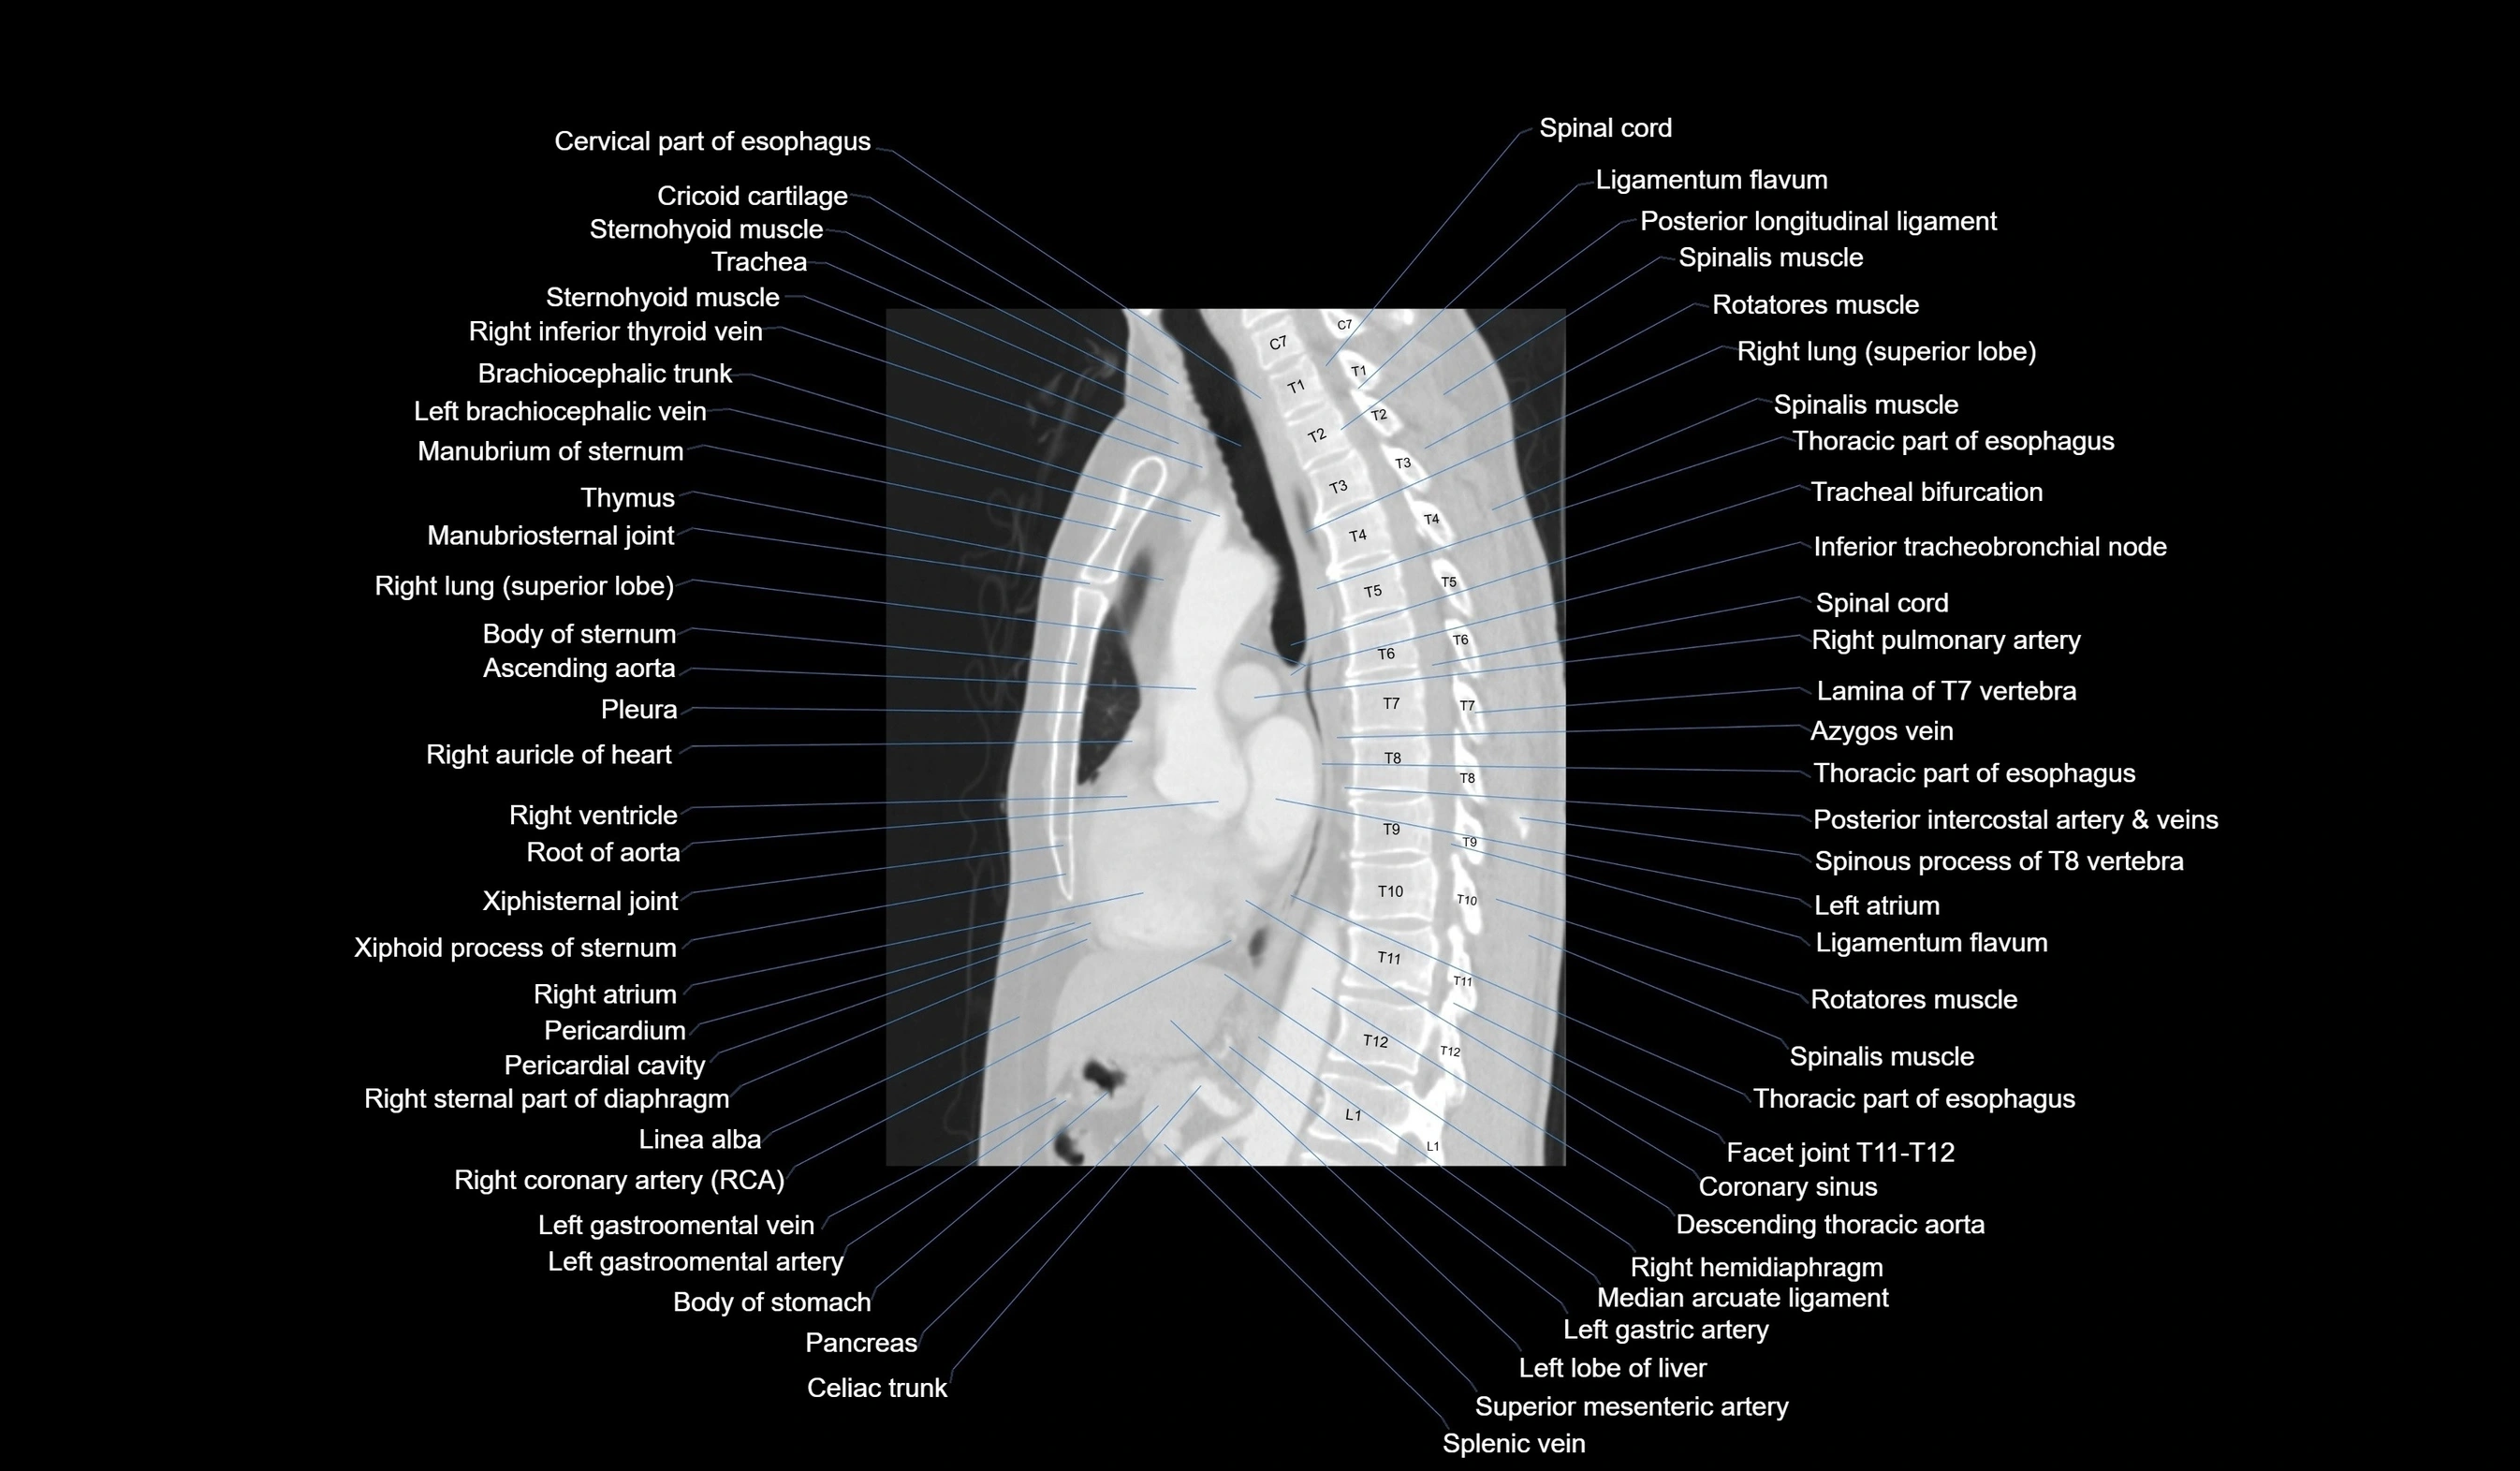

- T (Thoracic spine)

CT images